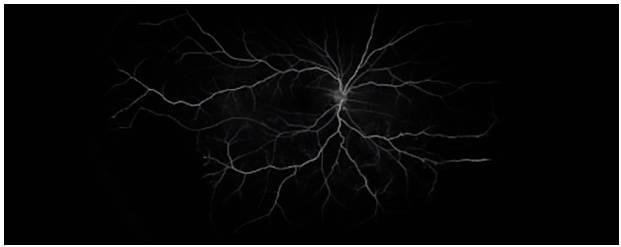

Fluorescein angiography showed that the infratemporal and peripheral non perfusion areas were wedge-shaped, the brightness decreased, and the perfusion time was normal (Fig. 3).

Fine lace collateral vessels can be seen near the non perfusion area, and there is no late leakage in the center.

Figure 3 Fluorescein angiography showed low fluorescence in the wedge-shaped area